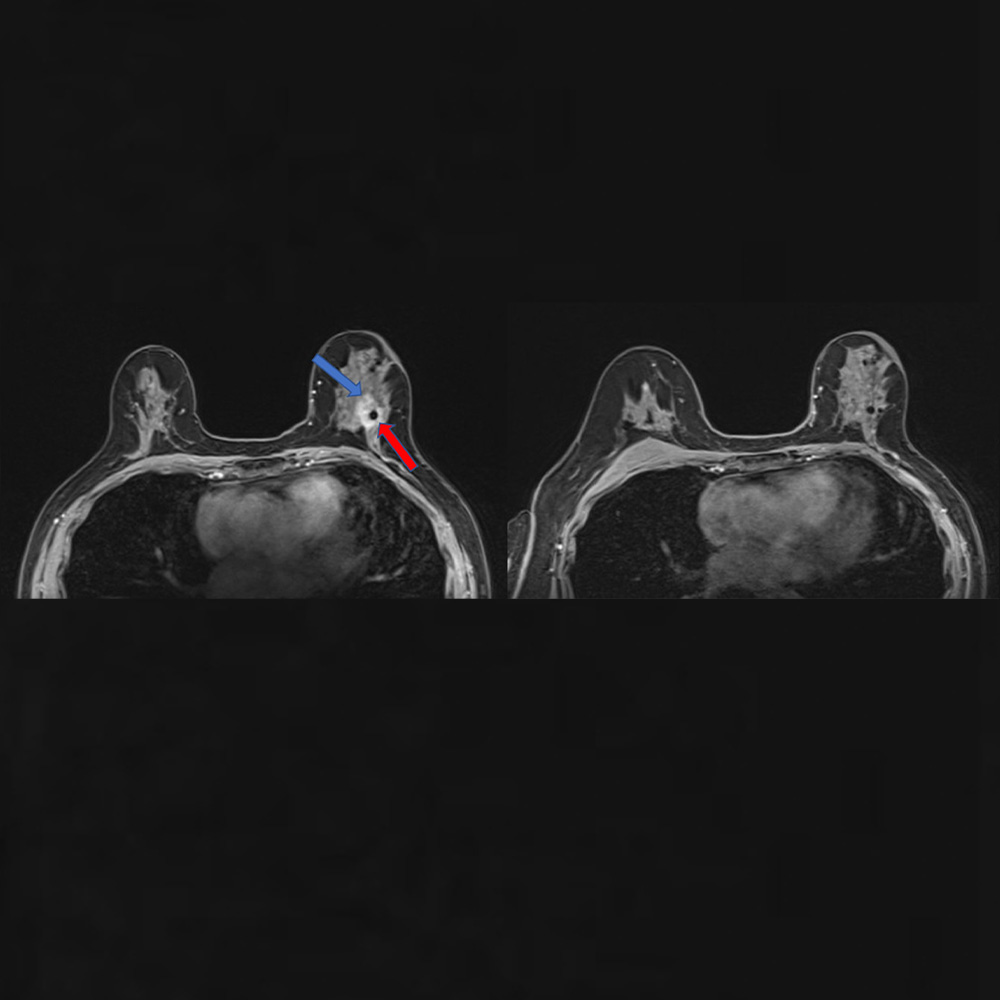

These two magnetic resonance imaging (MRI) scans were taken 10 months apart. On the left, the blue arrow points to the edge of a breast tumor, and the red arrow locates a biopsy clip, which appears as a black dot. The MRI on the right, which includes the biopsy clip, shows the tumor is gone after a single, targeted dose of radiation and antihormone therapy.

Early-stage, hormone-positive breast cancer accounts for 60%-75% of all breast cancers. Seeking a more time-efficient way to treat these patients, Dr. Rahimi and her colleagues tested a strategy in which 44 patients started treatment with a single dose of targeted radiation. While typical radiation therapy protocols call for 1.8-2.67 Gy (a measure of radiation strength) per day for 16 to 33 days, the researchers divided the study participants into three groups and gave each patient a single dose of 30, 34, or 38 Gy. The volunteers then went on hormone-blocking drugs and waited a median of 9.8 months until they underwent surgery to remove any residual tumor tissue.

In 72% of study participants, the surgeons found no residual tumor left, indicating that patients had a “pathological complete response.” An additional 21% of patients had a “near complete response,” meaning that their cancer was more than 90% eliminated.

When the researchers further analyzed the results, they found that time to surgery was the best predictor of response. The longer patients waited to undergo surgery, the more likely their tumors were to disappear, regardless of the radiation dose or tumor size. These results were probably due to the time it takes cells to die or be removed by the immune system after radiation therapy, Dr. Rahimi explained.